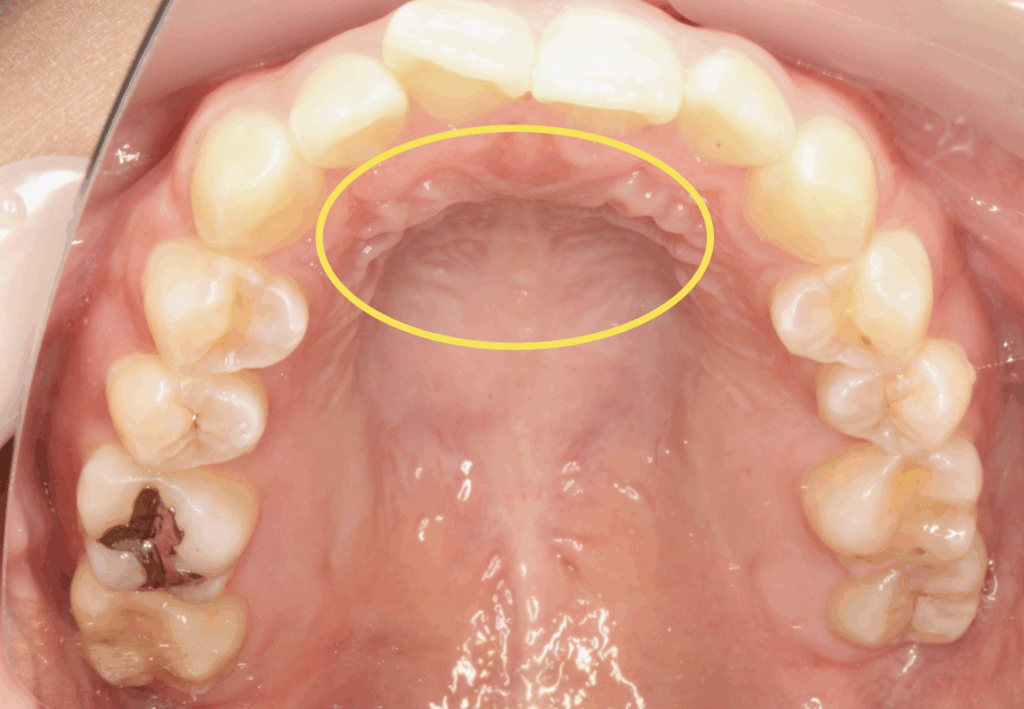

矯正治療中に「話しづらい」と感じたら ― 滑舌の変化と上手に付き合うためのポイント ― みなさま、こんにちは。石岡みらい矯正歯科・院長の丸岡亮です。 矯正装置をつけたあと、「話しづらくなった」「人に聞き返されること … 続きを読む 矯正治療中の滑舌について【茨城県石岡市の矯正歯科医院・石岡みらい矯正歯科】